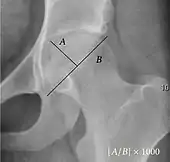

| Acetabular depth ratio | ![]() |

Deepness of acetabulum. | >250

|